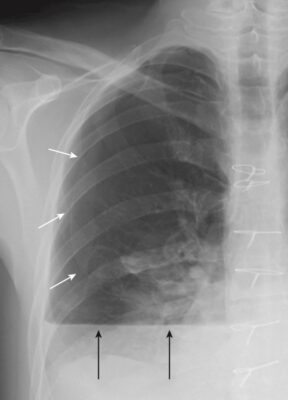

Mờ các góc sườn hoành (Blunting of the Costophrenic Angles)

Khi tràn dịch dưới phổi phát triển về kích thước, trước tiên nó sẽ lấp đầy và do đó làm mờ rãnh sườn hoành sau, có thể nhìn thấy ở phim phổi nghiêng. Điều này xảy ra với khoảng 75 mL chất dịch (Hình 4).

- Khi tràn dịch đạt đến kích thước khoảng 300 mL, nó làm mờ góc sườn hoành bên, có thể nhìn thấy trên phim X quang ngực thẳng (Hình 5).

- Cạm bẫy: Dày màng phổi do xơ hóa cũng có thể gây mờ góc sườn hoành.

- Giải pháp: Sẹo (ví dụ, do nhiễm trùng, phẫu thuật hoặc máu trong khoang màng phổi trước đó) đôi khi tạo ra hình dạng mờ kiểu dốc trượt tuyết đặc trưng, không giống như hình dạng như sụn chêm (meniscoid) của tràn dịch màng phổi (Hình 6).

- Dày màng phổi sẽ không thay đổi vị trí khi bệnh nhân thay đổi tư thế, khác với hầu hết các trường hợp tràn dịch.